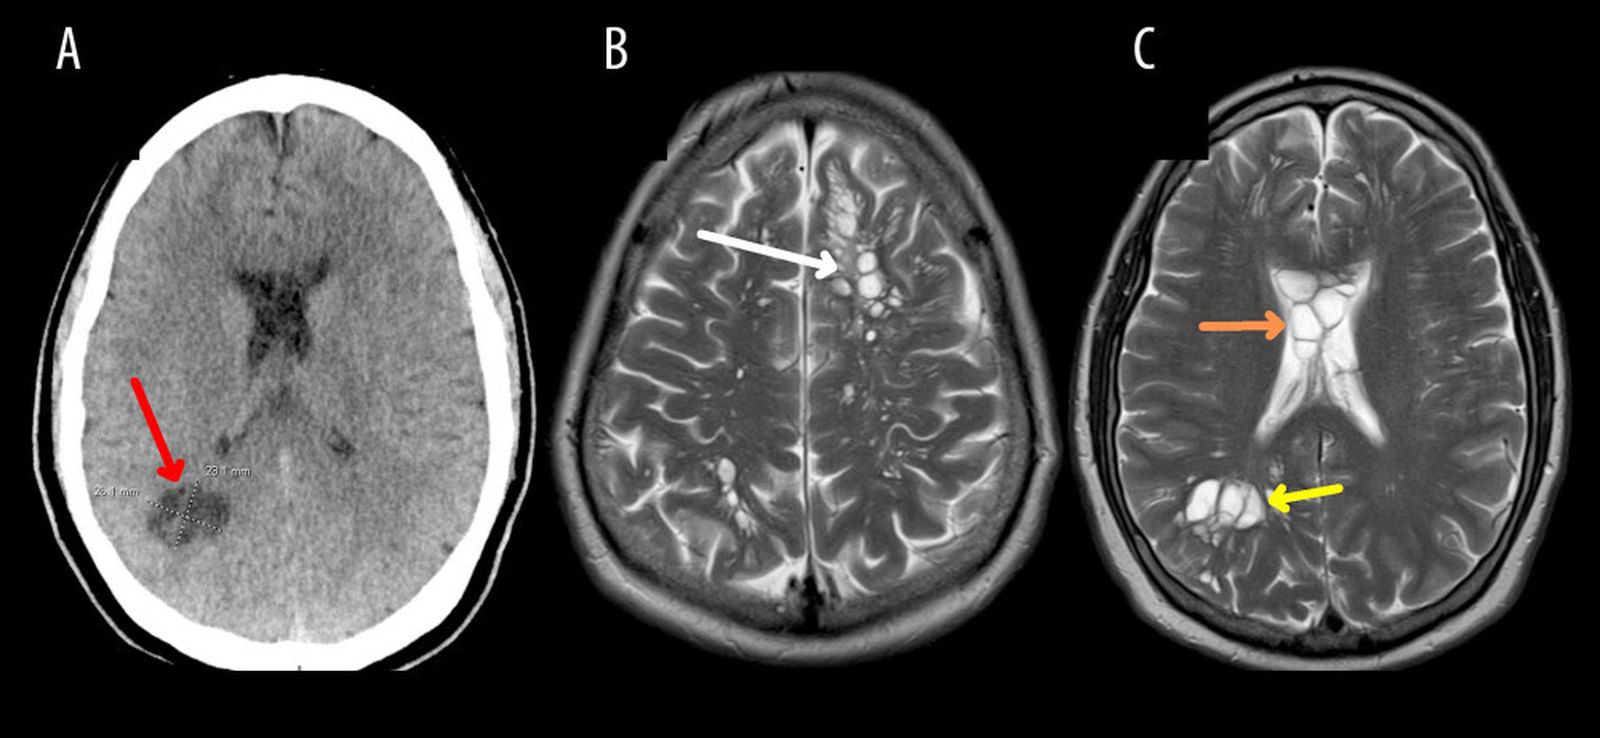

Fue entonces cuando los médicos realizaron una tomografía computarizada que reveló la presencia de numerosos quistes en su cerebro, esparcidos bilateralmente en el parénquima cortical profundo y la sustancia blanca periventricular. Inicialmente, se consideró que estos cambios podrían ser quistes neurogliales congénitos, pero una resonancia magnética posterior mostró signos de edema alrededor de los quistes, lo que suscitó preocupaciones de neurocisticercosis.

La neurocisticercosis, una forma de infección parasitaria del sistema nervioso causada por Tenia solium, es una condición poco común pero grave. En este caso, los exámenes de laboratorio revelaron la presencia de anticuerpos IgG específicos para la cisticercosis, confirmando el diagnóstico. El paciente fue tratado de inmediato con dexametasona para reducir el edema cerebral y se le administraron medicamentos antiparasitarios, albendazol y praziquantel, durante un período de 14 días.